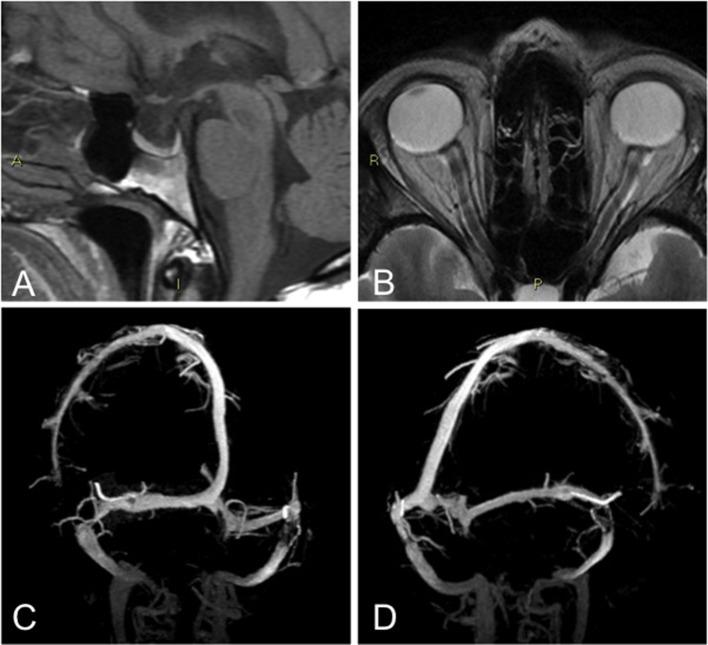

To determine the prevalence of Idiopathic intracranial hypertension without papilledema (IIHWOP) testing revised diagnostic criteria by Friedman in refractory chronic headache (CH) patients. This is a prospective observational study. Each patient underwent ophthalmologic evaluation and Optical Coherence Tomography; brain magnetic resonance venography (MRV) and a lumbar puncture (LP) with opening pressure (OP) measurement. CSF withdrawal was performed in patients with CSF OP > 200 mmH20. IIHWOP was defined according Friedman's diagnostic criteria. Effect of CSF withdrawal was evaluated clinically in a 6-month follow-up and with a MRV study at 1 month. Forty-five consecutive patients were enrolled. Five were excluded due to protocol violations. Analyses were conducted in 40 patients (32 F, 8 M; mean age 49.4 ± 10.8). None had papilledema. Nine patients (22.5%) had OP greater than 200 mmH2O, two of them above 250 mmH2O. Two (5%) had neuroimaging findings suggestive of elevated intracranial pressure. One of them (2.5%) met the newly proposed diagnostic criteria by Friedman for IIHWOP. After CSF withdrawal seven (77.8%) of the nine patients improved. No changes in neuroimaging findings were found. We found a low prevalence (2.5%) of IIHWOP in refractory CH patients according to current diagnostic criteria. In agreement with Friedman's criteria, our results confirm that a diagnosis of IIHWOP should be based on CSF OP and the combination of neuroradiological findings. However, where to set the CSF OP upper limit in IIHWOP needs further field testing. Although IIHWOP is a rare clinical condition, it should be considered and treated in refractory CH patients.

为了通过弗里德曼修订的诊断标准来确定难治性慢性头痛(CH)患者中无视乳头水肿的特发性颅内高压(IIHWOP)的患病率。这是一项前瞻性观察研究。每位患者均接受眼科评估和光学相干断层扫描;脑磁共振静脉血管造影(MRV)以及测量初压(OP)的腰椎穿刺(LP)。脑脊液初压>200 mmH20的患者进行脑脊液引流。IIHWOP根据弗里德曼的诊断标准定义。在6个月的随访中对脑脊液引流的效果进行临床评估,并在1个月时进行MRV研究。连续纳入45例患者。5例因违反方案被排除。对40例患者(32例女性,8例男性;平均年龄49.4±10.8岁)进行分析。均无视乳头水肿。9例患者(22.5%)的初压大于200 mmH2O,其中2例高于250 mmH2O。2例(5%)有提示颅内压升高的神经影像学表现。其中1例(2.5%)符合弗里德曼新提出的IIHWOP诊断标准。脑脊液引流后,9例患者中的7例(77.8%)病情改善。神经影像学表现无变化。根据当前诊断标准,我们发现在难治性CH患者中IIHWOP的患病率较低(2.5%)。与弗里德曼的标准一致,我们的结果证实IIHWOP的诊断应基于脑脊液初压和神经放射学表现的综合。然而,在IIHWOP中脑脊液初压上限应设定在哪里需要进一步的实地测试。虽然IIHWOP是一种罕见的临床情况,但在难治性CH患者中应予以考虑和治疗。